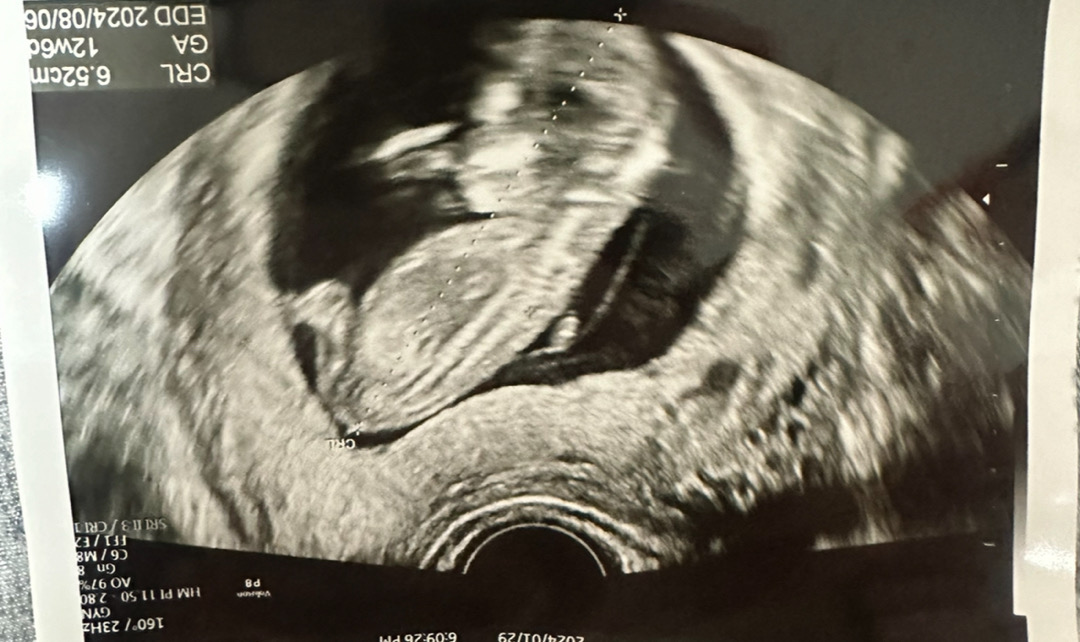

12주차 2일 성별 확인 되실까요?

너무 궁금하네용 여러분 의견 남겨주시면 감사하겠습니당 😍

저사진으로는 보기가 힘드네용 ㅠ

제 느낌은 딸요!